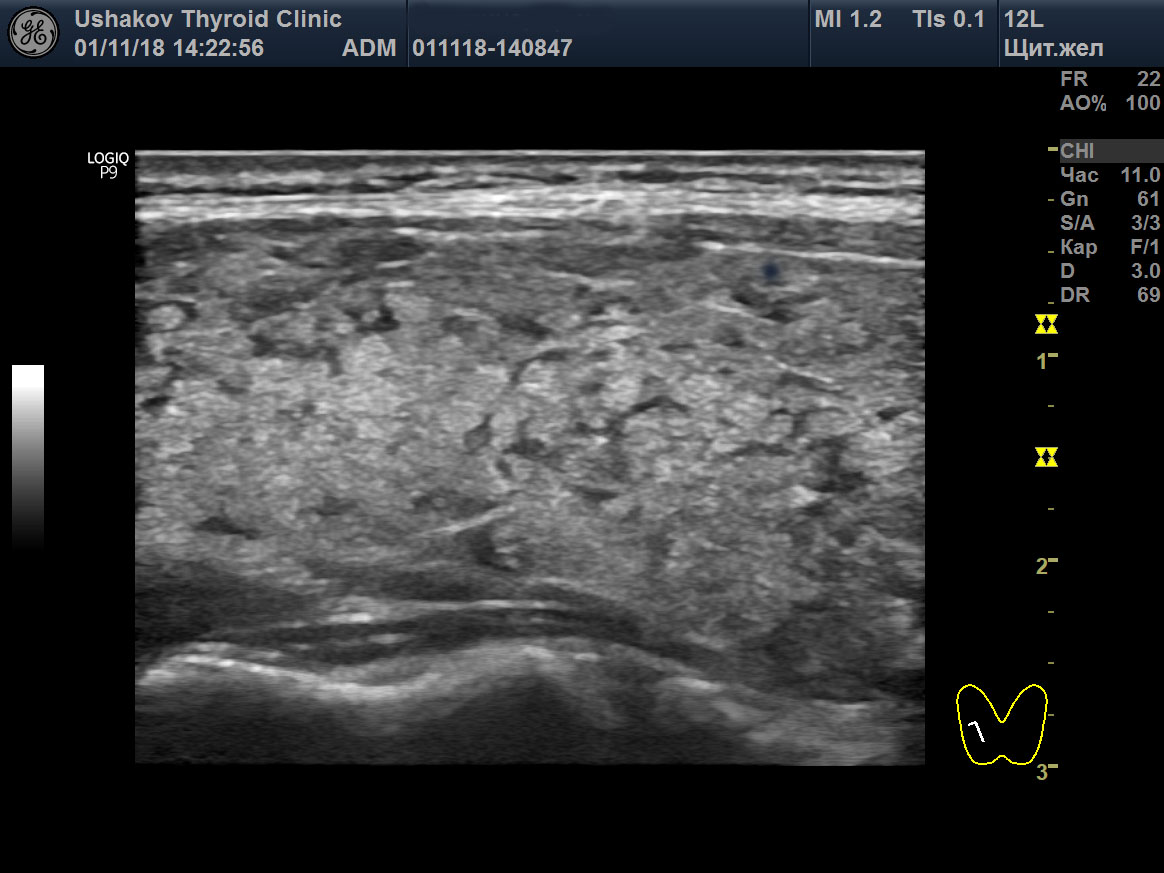

Пример такого восстановления щитовидной железы при аутоиммунном тиреоидите представлен на

рис. 4. Этот пример показывает, как за счёт регенерации в ЩЖ пациентки через 10 месяцев значительно уменьшилось количество долек с признаками деструкции и замещения лимфоидной тканью (округлых гипоэхогенных участков), являющихся признаком тиреоидита Хашимото. Вместо лимфоидной ткани появилась полноценная гормонообразующая ткань ЩЖ. Одновременно с репаративным восстановлением структуры ЩЖ значительно уменьшилась активность иммунной помощи железе, что заметно по уменьшению в крови титра антител к ТПО и ТГ.

Рисунок 4 (начало) Правая доля щитовидной железы у пациентки 35 лет (продольная проекция). Слева – состояние доли 13.08.18 (АТ-ТПО 775 МЕ/л [<5,6], АТ-ТГ 30 МЕ/л [<4,1]), справа – 10.06.19 (АТ-ТПО 195 МЕ/л [<5,6], АТ-ТГ 9,5 МЕ/л [<4,1]). Гормональные медикаменты никогда не использовала.

|

Рисунок 4 (окончание) За 10 месяцев произошло значительное улучшение структуры ЩЖ. В ткани щитовидной железы значительно уменьшилось количество лимфоидной ткани в дольковых сегментах, осталось очень малое количество мелких долек с признаками деструкции и лимфоидного замещения.